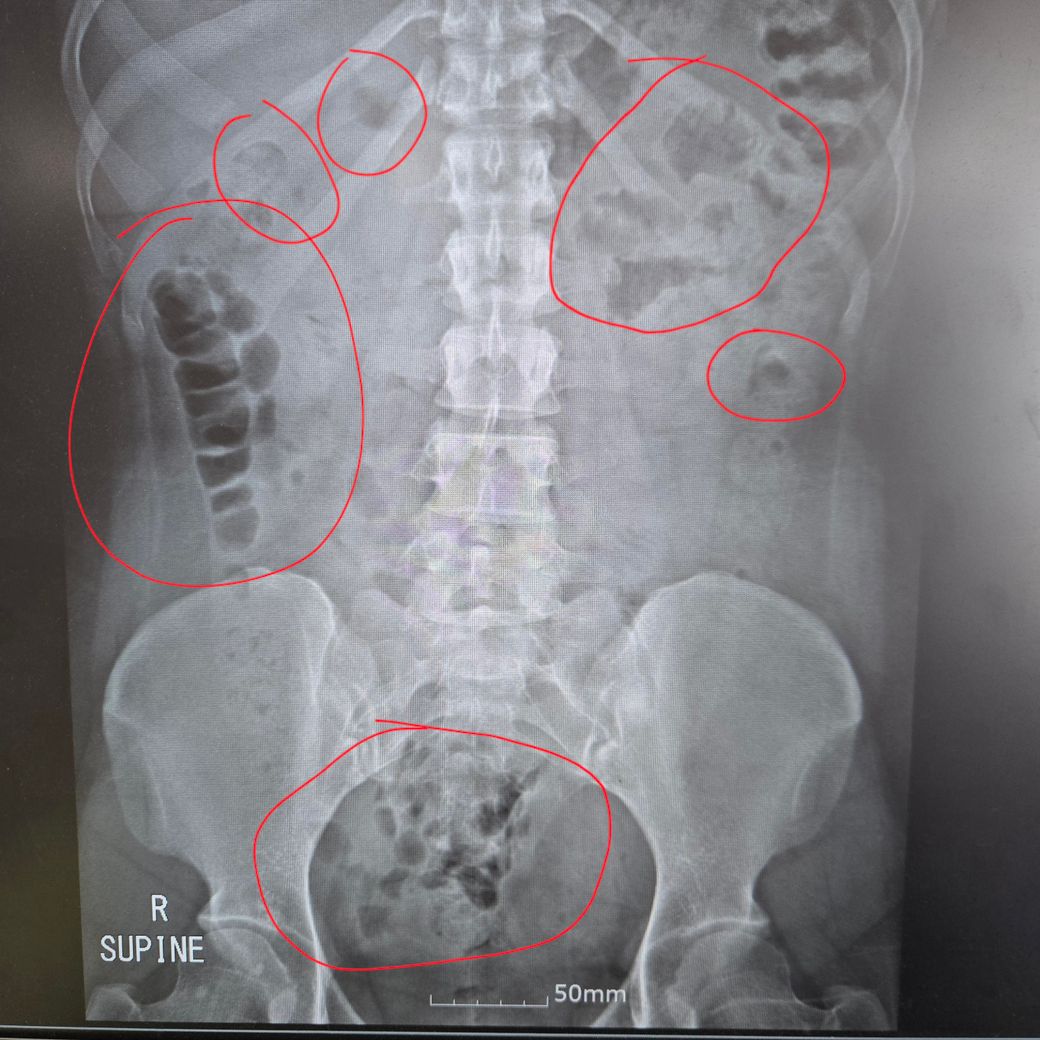

CT?CR? 찍었는데 동그라미 그려진 부분 뭔가용?...

사진에 동그라미 그려진 부분에 이상한 흐믈건한것들이랑 찐한 응가모양이랑 이것저것 뭔가용?.. 그리고 따로 문제는 없나용? 진료보긴했는데 너무 대충 봐주셔서 여기에도 올려봐요ㅠㅠ

사실 복부 X ray 로 자세한것을 알기는 어렵긴 합니다. 가스와 대변이 대장에 있는것은 원래 당연한 거고,, 별로 특이소견 없어보이네요

흐물흐물은 장내가스

대변은 대변이네요

말씀하신 사진의 표시한 부분은 장 bowel 입니다

정상구조물이니 너무 걱정하지 않으셔도 됩니다.